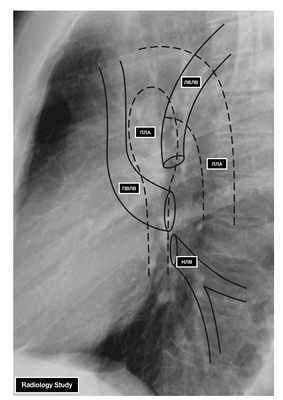

Из двух правых легочных вен больший диаметр имеет верхняя, так как по ней оттекает кровь от двух долей правого легкого (верхней и средней). Из двух левых легочных вен больший диаметр имеет нижняя вена. В воротах правого и левого легких легочные вены занимают их нижнюю часть. В задней верхней части корня правого легкого расположен главный правый бронх, кпереди и книзу от него — правая легочная артерия.

- ЛВЛВ — левая верхняя легочная вена

- ПВЛВ — правая верхняя легочная вена

- НЛВ — нижняя легочная вена

- ПЛА — правая легочная артерия

- ЛЛА — левая легочная артерия

У левого легкого сверху находится легочная артерия, кзади и книзу от нее — левый главный бронх. У правого легкого легочные вены лежат ниже артерии, следуют почти горизонтально и на своем пути к сердцу располагаются позади верхней полой вены, правого предсердия и восходящей части аорты. Обе левые легочные вены, которые несколько короче правых, находятся под левым главным бронхом и направляются к сердцу также в поперечном направлении, кпереди от нисходящей части аорты. Правые и левые легочные вены, прободая перикард, впадают в левое предсердие (их конечные отделы покрыты эпикардом).